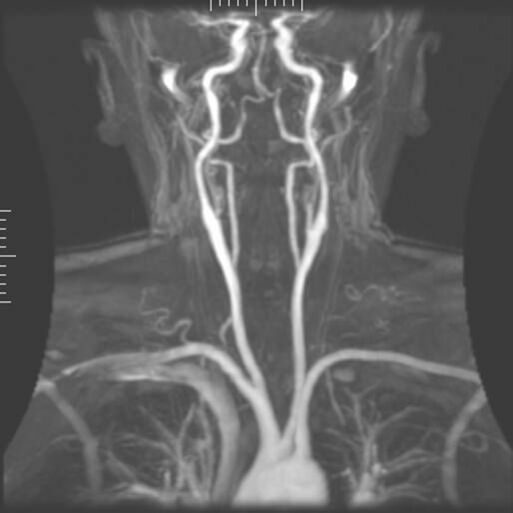

Вну́тренняя со́нная арте́рия (лат. artéria carótis intérna) — парная крупная артерия шеи и головы. Берёт своё начало от бифуркации общей сонной артерии, где последняя делится на неё и наружную сонную артерии[1].

Внутренняя сонная артерия является конечной ветвью общей сонной артерии. Начинается приблизительно с уровня третьего шейного позвонка, где общая сонная артерия разделяется на неё и более поверхностную ветвь — наружную сонную артерию.

Шейный сегмент, или С1, внутренней сонной артерии располагается от бифуркации общей сонной артерии до наружного отверстия сонного канала височной кости, кпереди от яремного отверстия.

В самом начале внутренняя сонная артерия несколько расширена. Эта часть артерии больше известна как каротидный синус. Восходящая часть шейного сегмента располагается дистальнее от синуса, где сосудистые стенки снова идут параллельно.

Далее внутренняя сонная артерия идёт вертикально вверх и вступает в полость черепа через сонный канал. На протяжении этой части пути она лежит спереди от поперечных отростков первых трёх шейных позвонков (С1—С3). В области сонного треугольника шеи артерия располагается относительно поверхностно. Здесь она лежит позади и кнаружи от наружной сонной артерии, сверху пересекается грудино-ключично-сосцевидной мышцей, и прикрыта глубокой фасцией, платизмой, собственной оболочкой. Далее артерия проходит под околоушной слюнной железой, будучи пересекаемой подъязычным нервом, двубрюшной мышцей, шилоподъязычной мышцей, затылочной артерией и задней ушной артерией. Выше внутренняя сонная артерия отграничивается от наружной сонной артерии посредством шилоязычной и шилоглоточной мышц, верхушкой шиловидного отростка и шилоподъязычной связки, языкоглоточного нерва и глоточных ветвей блуждающего нерва.